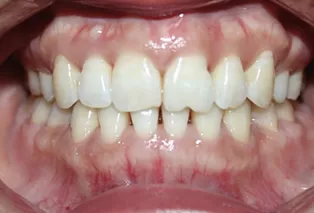

Photos intra-orales